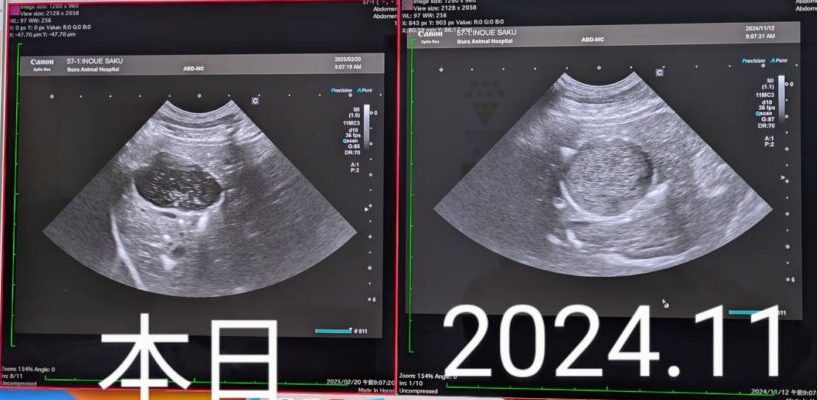

それがこちら↓

胆泥症のお薬は

1日2回から

1回に減薬できることになり

泥がかなり減っていて

獣医さんもびっくり

されるほど

最終面談の時も

始める前と今とを

比較するため写真で見比べて